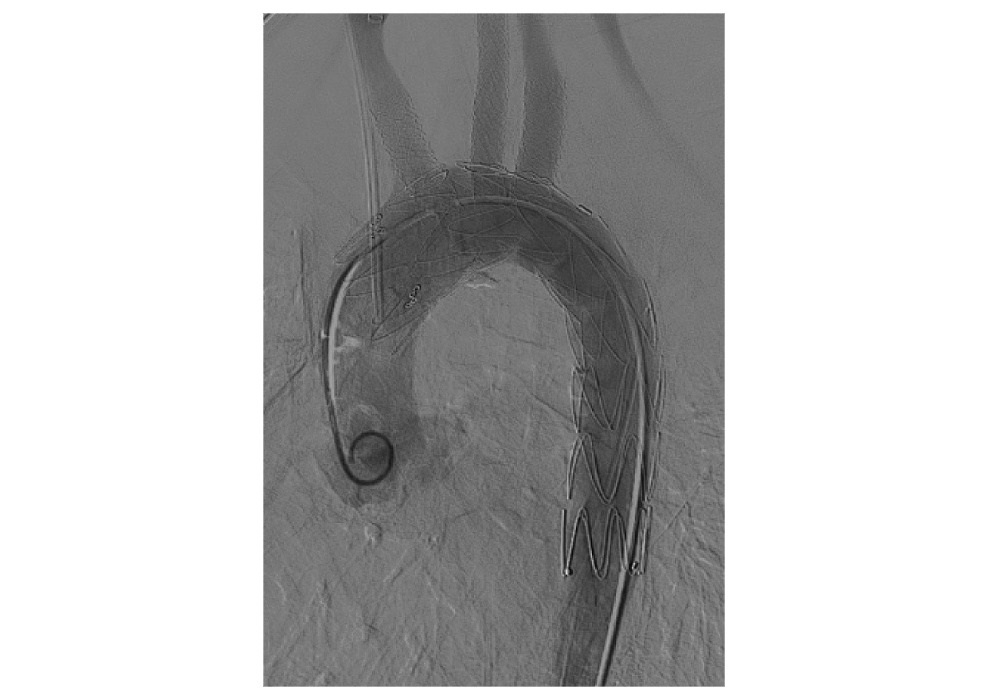

После успешной имплантации грудного графта были последовательно имплантированы стент-графты в артерии головы минимальным давлением. (рис. ниже)

На заключительной аортографии грудной стент-графт и его бранши проходимы, кровоток по аорте и артериям - магистральный, псевдоаневризмы не визуализируются, то есть, выключены из кровотока. (рис. ниже)